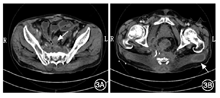

入院后查体:体温39 ℃,消瘦(体重指数16.65 kg/m2),中下腹轻压痛,腰骶部可见3处皮肤瘘口伴脓性分泌物。血白细胞计数8.51×109/L,中性粒细胞比例84.2%,血红蛋白69 g/L,血小板计数335×109/L。白蛋白24 g/L,红细胞沉降率87 mm/h,C反应蛋白120 mg/dl。腰骶部脓性分泌物培养结果示肺炎克雷伯菌、光滑假丝酵母菌阳性。结肠镜进镜至距肛缘约60 cm见结肠内瘘口,局部肉芽组织增生,降结肠及脾曲见另两处瘘口形成(图1)。窦道造影可见水溶性造影剂经皮进入窦道,中下腹部多发窦道显影,与小肠、横结肠相通(图2)。小肠CT示克罗恩病术后改变,空肠、盆组回肠克罗恩病活动期改变伴小肠-结肠管内瘘形成,病变肠管与双侧髂肌、右侧闭孔内肌、骶前区多发瘘管形成;骶骨周围、左侧坐骨直肠窝蜂窝织炎及脓肿;双侧臀大肌多发脓肿;右侧输尿管下段与病变肠管粘连,右侧输尿管积水(图3)。磁共振尿路造影示右侧输尿管下段狭窄伴右肾及输尿管中上段扩张积水(图4)。